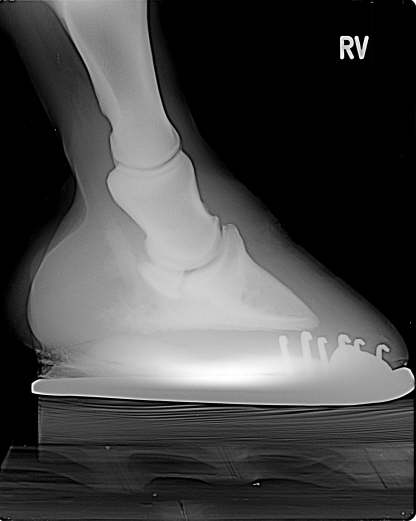

Seitliches Röntgen

Gebrochene Zehenachse, flacher Hufbeinwinkel, Hufknorpelverknöcherung